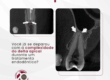

Nesta análise tridimensional de perda óssea, a tomografia a evidencia significativamente ao redor do implante, permitindo uma avaliação detalhada da progressão da reabsorção e seu impacto estrutural.

O que os cortes tomográficos revelam?

Comprometimento ósseo peri-implantar – A imagem mostra uma área de reabsorção óssea ao redor do implante, indicando um possível processo inflamatório ou falha na osseointegração. Em síntese, a extensão da perda pode impactar a estabilidade do implante e a longevidade da reabilitação.

Atingimento da cortical óssea – A análise tridimensional de perda óssea em diferentes planos permite observar o envolvimento da cortical vestibular e lingual, que pode estar afinada ou rompida. Isso, um fator determinante para a conduta clínica e necessidade de regeneração óssea.

Espaço biológico e adaptação da prótese – A tomografia também permite avaliar se o desenho protético está influenciando a resposta óssea. Desse modo, observando possíveis sobrecargas que podem estar acelerando o processo de reabsorção.

Proximidade com estruturas anatômicas – É possível visualizar a relação do implante com estruturas críticas, como o canal mandibular.

Portanto, a tomografia não apenas confirma a presença da perda óssea. Mas também, fornece dados essenciais para mensurar sua extensão, avaliar sua relação com o implante e definir a abordagem ideal para tratamento e controle do caso.